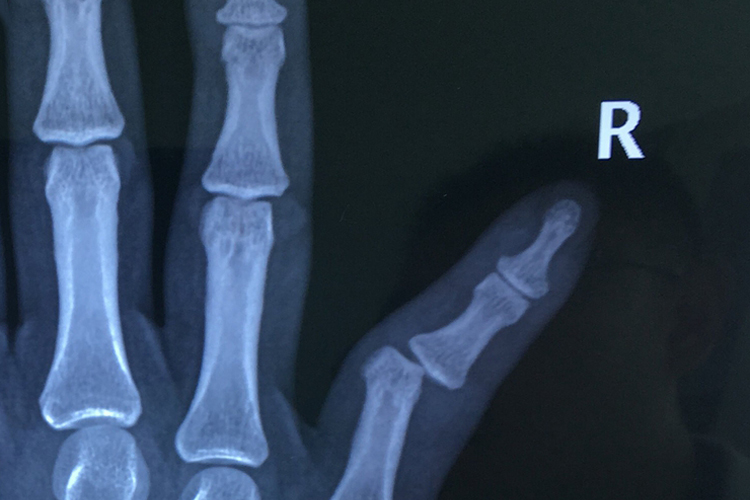

小手指错位通常指关节脱位,表现为局部肿胀、疼痛,X光片可见指骨脱离原有关节,可通过手法复位后固定,恢复正常关节形态。

小手指错位通常为小指关节脱位,可通过手法复位后进行固定,并配合药物治疗,以促进恢复。恢复过程中需通过X光片确认关节和两侧骨骼位置的恢复情况,最初可见关节明显脱位,两侧指骨不对应;固定时可见关节两侧骨骼恢复正常位置;恢复后可见关节两侧骨骼在去除固定后,仍然维持正常位置,关节形态恢复正常。